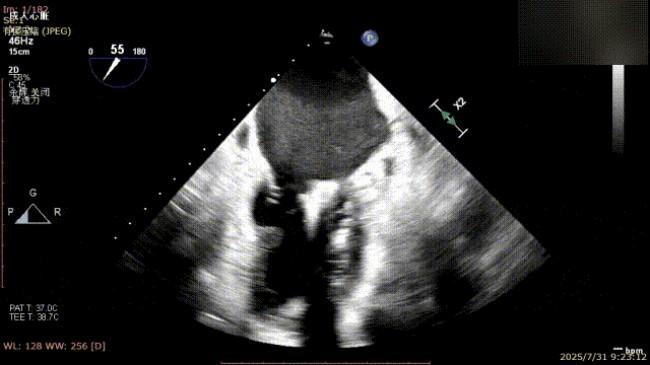

手术过程中,麻醉与围术期医学科副主任医师马金本确保麻醉过程平稳。心脏大血管外科主治医师董明亮穿刺股静脉置入血管鞘,并在心脏超声科梁皓主任及段福建教授TEE引导下,顺利穿刺房间隔,房间隔穿刺高度4.9cm。随后,在王安彪主任以及刘洋教授指导、心脏超声科梁皓主任TEE引导下,董明亮医师沿输送系统将延展呈“一字型”状态的国产夹合器送至左房,缓慢关闭夹合器并进行弹道测试。调整夹合器位置和方向后,董明亮医师再次将夹合器延展呈“一字型”完成跨瓣,避免发生腱索缠绕,成功捕获瓣叶后关闭夹合器,二尖瓣反流显著下降。夹合器完全解离后,超声示二尖瓣反流程度显著下降,残余反流0,平均跨瓣压差1mmHg,手术圆满成功。

解离后瓣叶及反流

解离后三维

平均跨瓣压差